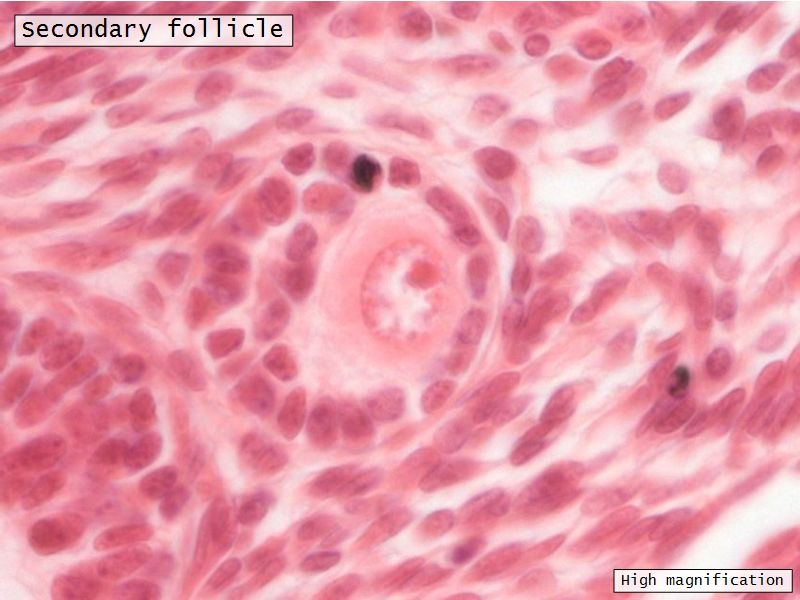

Follicular maturation

- Primordial follicle

- Growing follicle

- Primary follicle

- Secondary follicle

- Mature follicle (Graafian)

Components of a follicle

- Theca

- externa

- interna

- basal lamina

- Granulosa cells

- Antrum

- Cumulus oophorus >> Corona radiata

- Oocyte